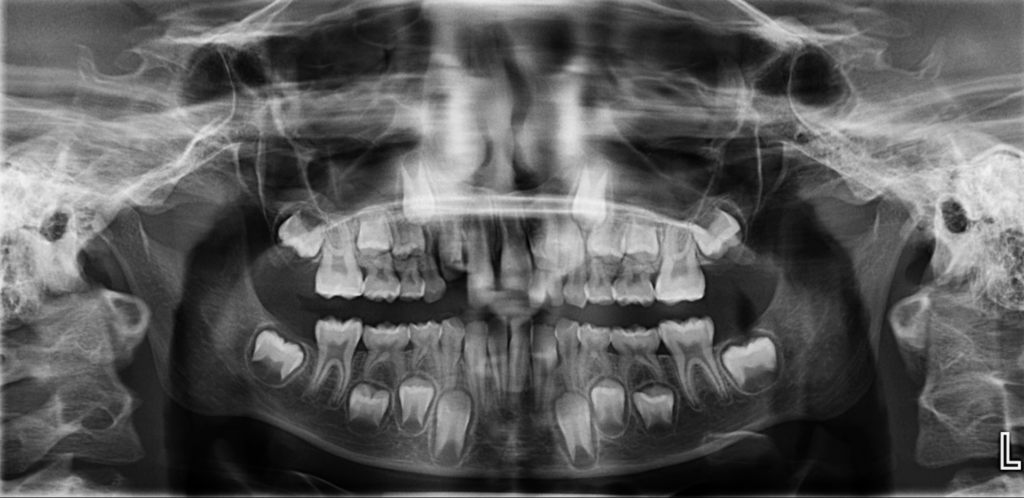

En la radiografía panorámica (Figura 1), se observa pieza supernumeraria en evolución intraósea ubicada entre la piezas 22 y 23, además de una alteración en la morfologia coronaria de pieza 22.

Además se observa la persistencia de piezas deciduas 61 y 62.

Radiografia Panorámica